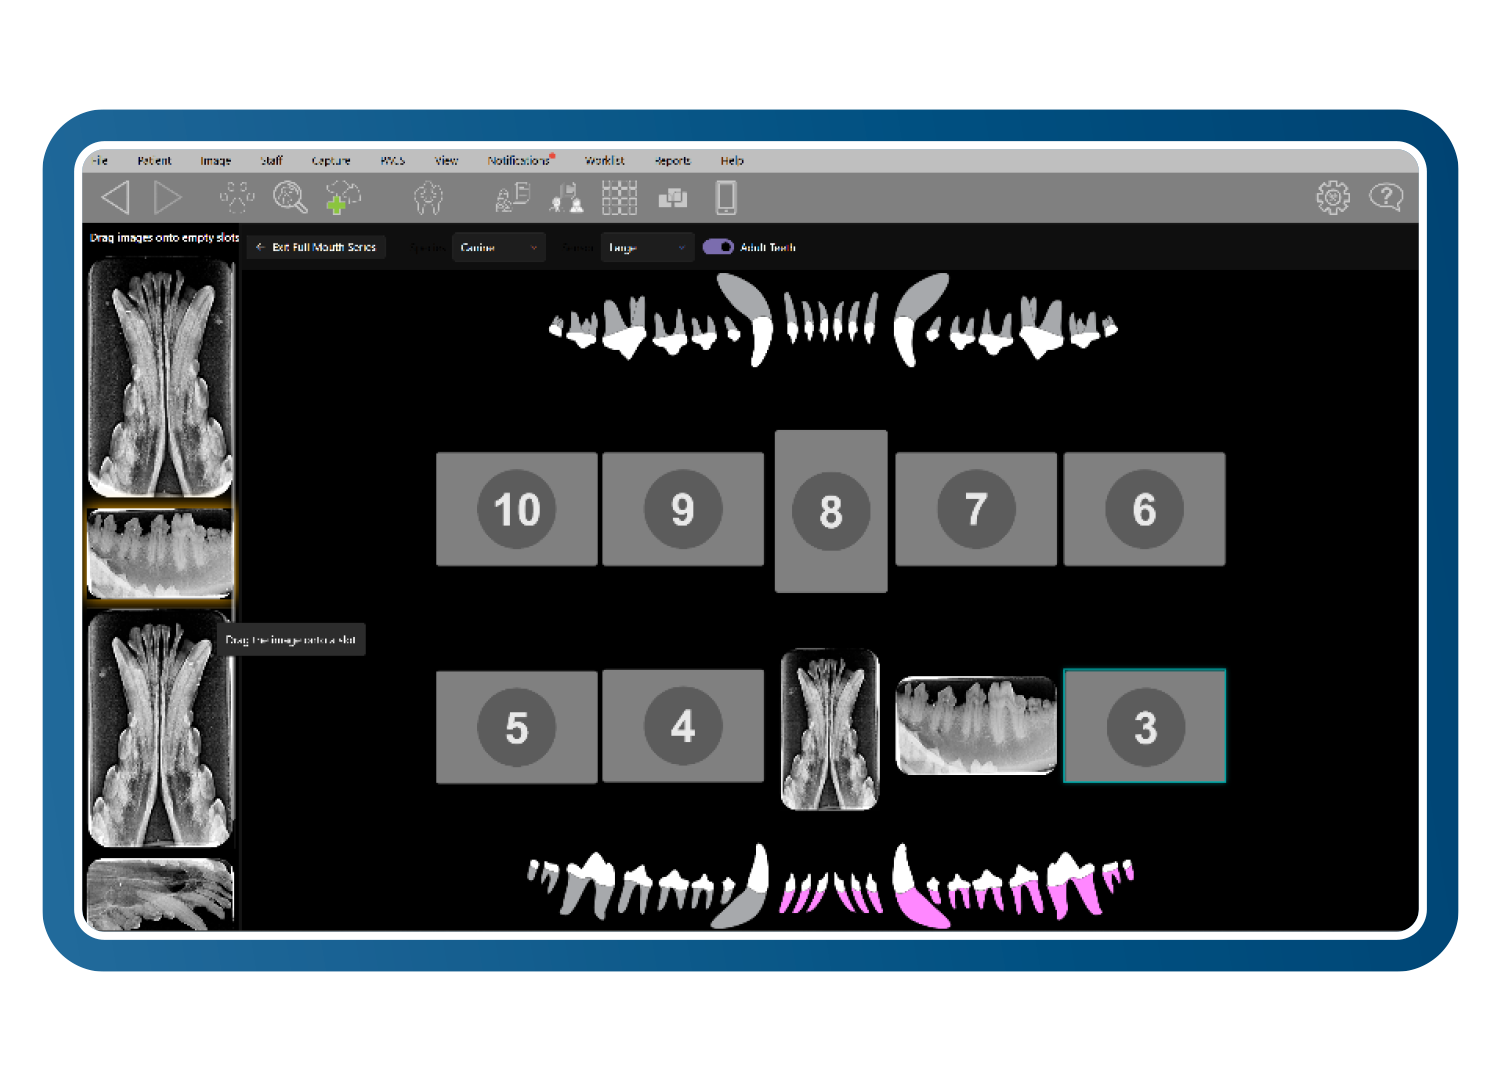

Diseños intuitivos de boca completa y formato libre

Cree conjuntos de imágenes diagnósticas claros y completos utilizando diseños intuitivos de boca completa y formato libre para múltiples especies. Las imágenes se colocan automáticamente en la posición correcta, con una edición sencilla mediante arrastrar y soltar. Combine radiografías y fotografías para presentar una historia diagnóstica coherente y fácil de entender.